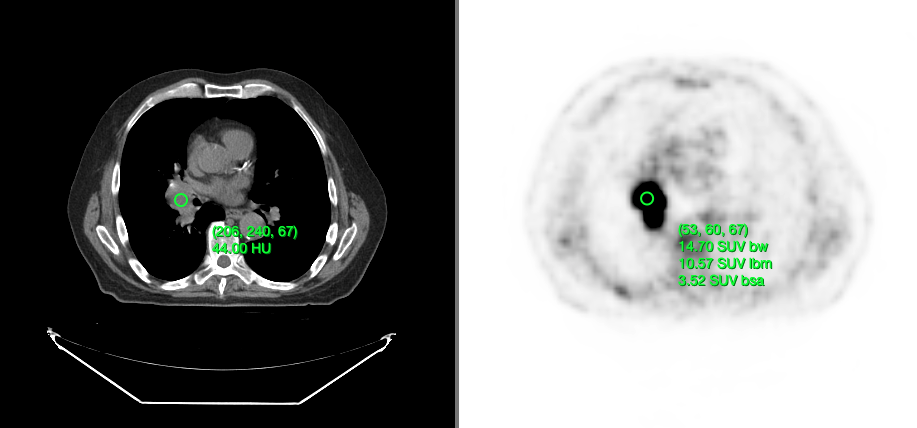

• Getting the underlying value for a voxel (Probe Tool)

Dynamic tool statistics

Cornerstone3DTools is capable of calculating dynamic statistics based on the modality of the volume being rendered. For instance, for CT volumes a ProbeTool will give Hounsfield Units and for PET it will calculate SUV stats.